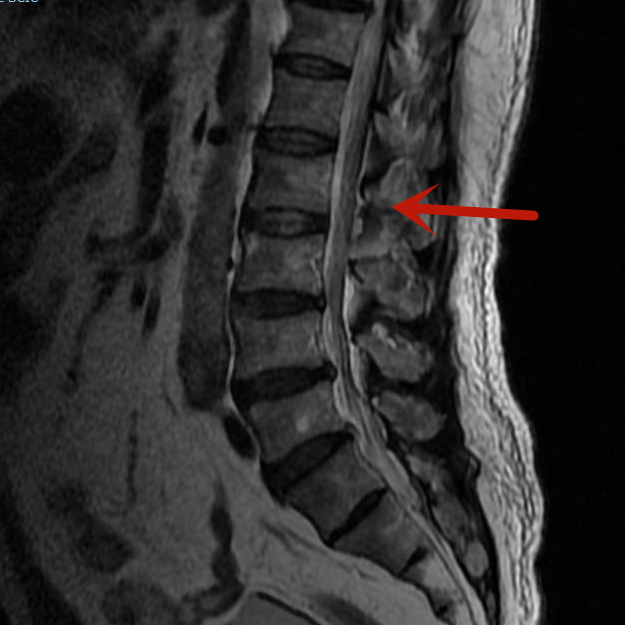

近期,梁先生因雙下肢麻木到我院脊柱骨科住院治療。腰椎磁共振檢查顯示患者的腰2-3椎管內腫瘤,很大可能性是血管瘤,若不及時手術治療,隨著腫瘤的生長、神經長時間受壓,將可能導致雙下肢癱瘓、大小便失禁等嚴重后果。

術前影像

患者腫瘤的大小約3.5cm×1.5cm,別看腫瘤不大,但要在內鏡下完全通過0.8cm大小的切口進行腫瘤后方的椎板切除減壓、腫瘤與周圍神經的分離、腫瘤的暴露、腫瘤的徹底切除,需要嫻熟的內鏡操作技術。